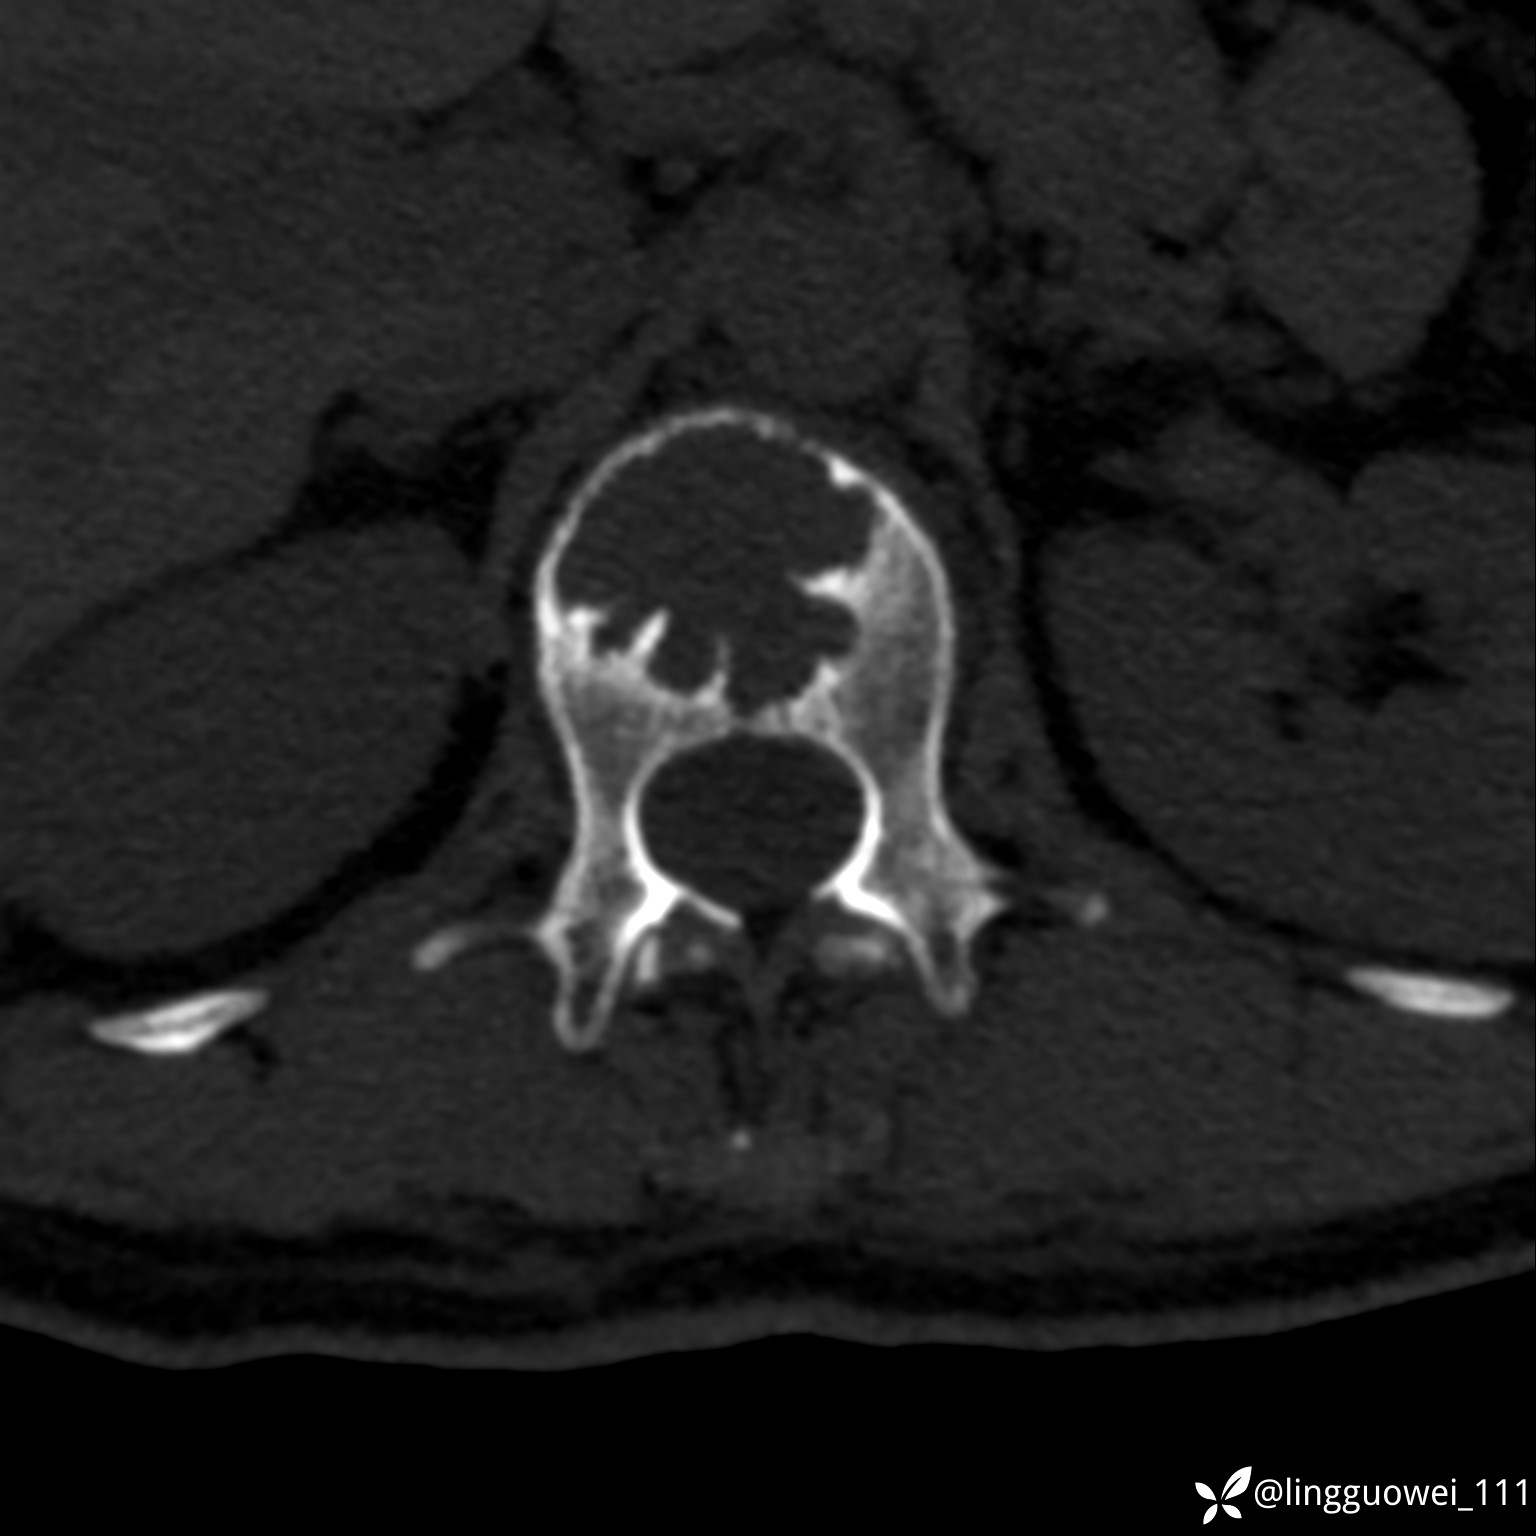

病例女,39岁,腰痛来诊,只有CT可能要鉴别诊断,而MR可以定性吗?

患者性别:女

患者年龄:39岁

主诉:腰痛